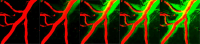

The researchers measured the performance of the brain’s cleansing cycle by injecting a tracer into the cerebrospinal fluid of mice and using high-resolution microscopy to capture time-lapse images of the tracer in the glymphatic system.

Cleaning the brain. A green tracer fluid flows through the brain's glymphatic system, a recently discovered waste disposal system. The system moves waste along the outer edges of the brain's blood vessels (red). Images provided by Kai Chen.